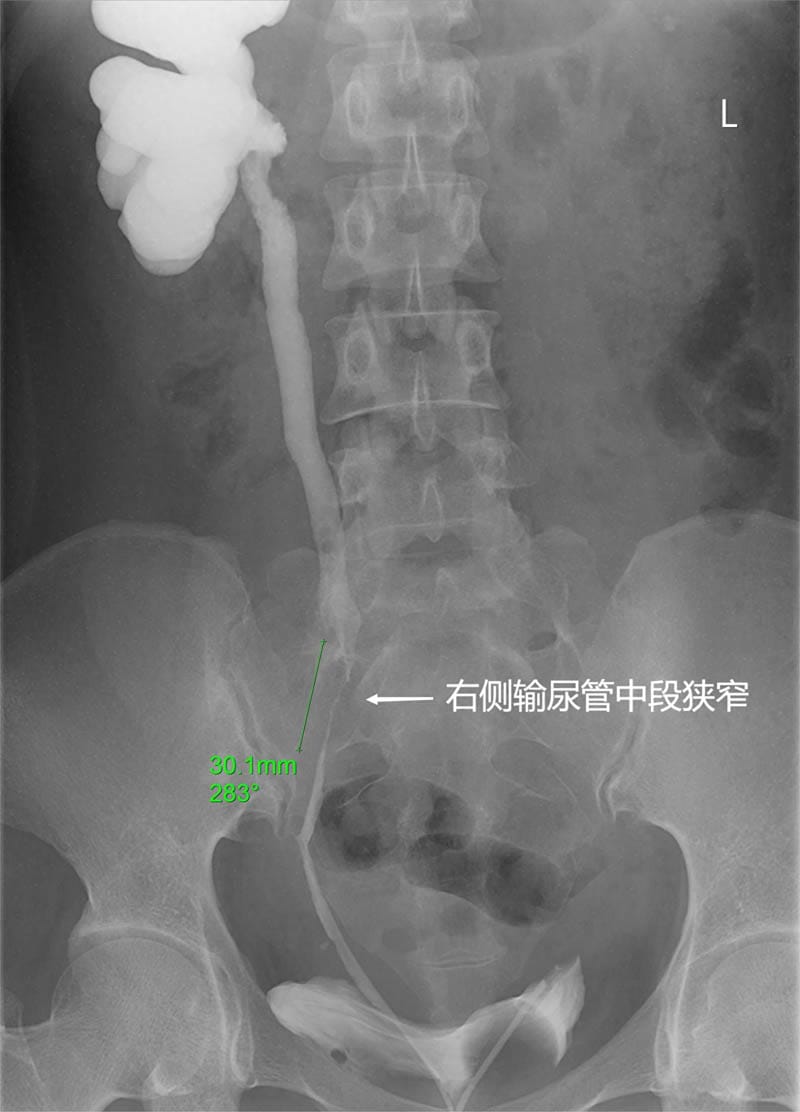

患者朱某,女性,40岁,因“双侧DJ管置入术后1月余”入住南华大学附属第二医院东院泌尿外科,患者既往有多次右输尿管结石手术史,今年7月再次因“左输尿管上段结石并左肾积水;双肾多发结石;右输尿管中段狭窄并右肾中度积水”在我院全麻下行“输尿管软镜下左肾结石、左输尿管结石钬激光碎石术+右输尿管中段狭窄扩张术+右输尿管支架管置入”手术治疗,术后恢复良好。此次为进一步处理“右输尿管中段狭窄”入院,因长期携带输尿管支架管,不仅影响剧烈活动,还可能引发反复尿路感染、疼痛、血尿等支架管刺激征,严重影响她的正常生活与工作,患者对此非常困扰。泌尿外科副主任兼东院泌尿外科主任李志军博士带领团队经过慎重探讨,在成功开展腹腔镜膀胱瓣代输尿管成形修复长段输尿管狭窄(6cm)的技术基础上,为患者拟定手术方案:腹腔镜联合输尿管镜输尿管狭窄段切除,膀胱瓣代输尿管或阑尾代输尿管成形术。

李志军博士带领手术团队采用双镜联合技术,先在腹腔镜下游离右输尿管,再利用输尿管镜精准定位输尿管的狭窄段,充分游离后确认狭窄段长约3厘米,输尿管周围严重粘连,右侧髂内动脉完全粘连于狭窄段后下壁,输尿管中上段管壁明显炎性增厚、张力高、弹性差,如强行狭窄段切除+断端吻合极其困难,且需离断右侧髂内动脉,术后容易出现输尿管吻合口缺血、漏尿、再发狭窄等并发症。在与患者家属深入沟通后,遂决定采用自身阑尾代输尿管。在腹腔镜下进行阑尾切除,剖开阑尾及输尿管狭窄部,分别将阑尾瓣的近远端和输尿管近远端进行吻合,“移花接木”般完美的恢复了右输尿管的连续性和通畅性,术中输尿管镜探查输尿管阑尾吻合腔通畅,手术顺利完成,术后恢复良好,右肾积水明显减轻。